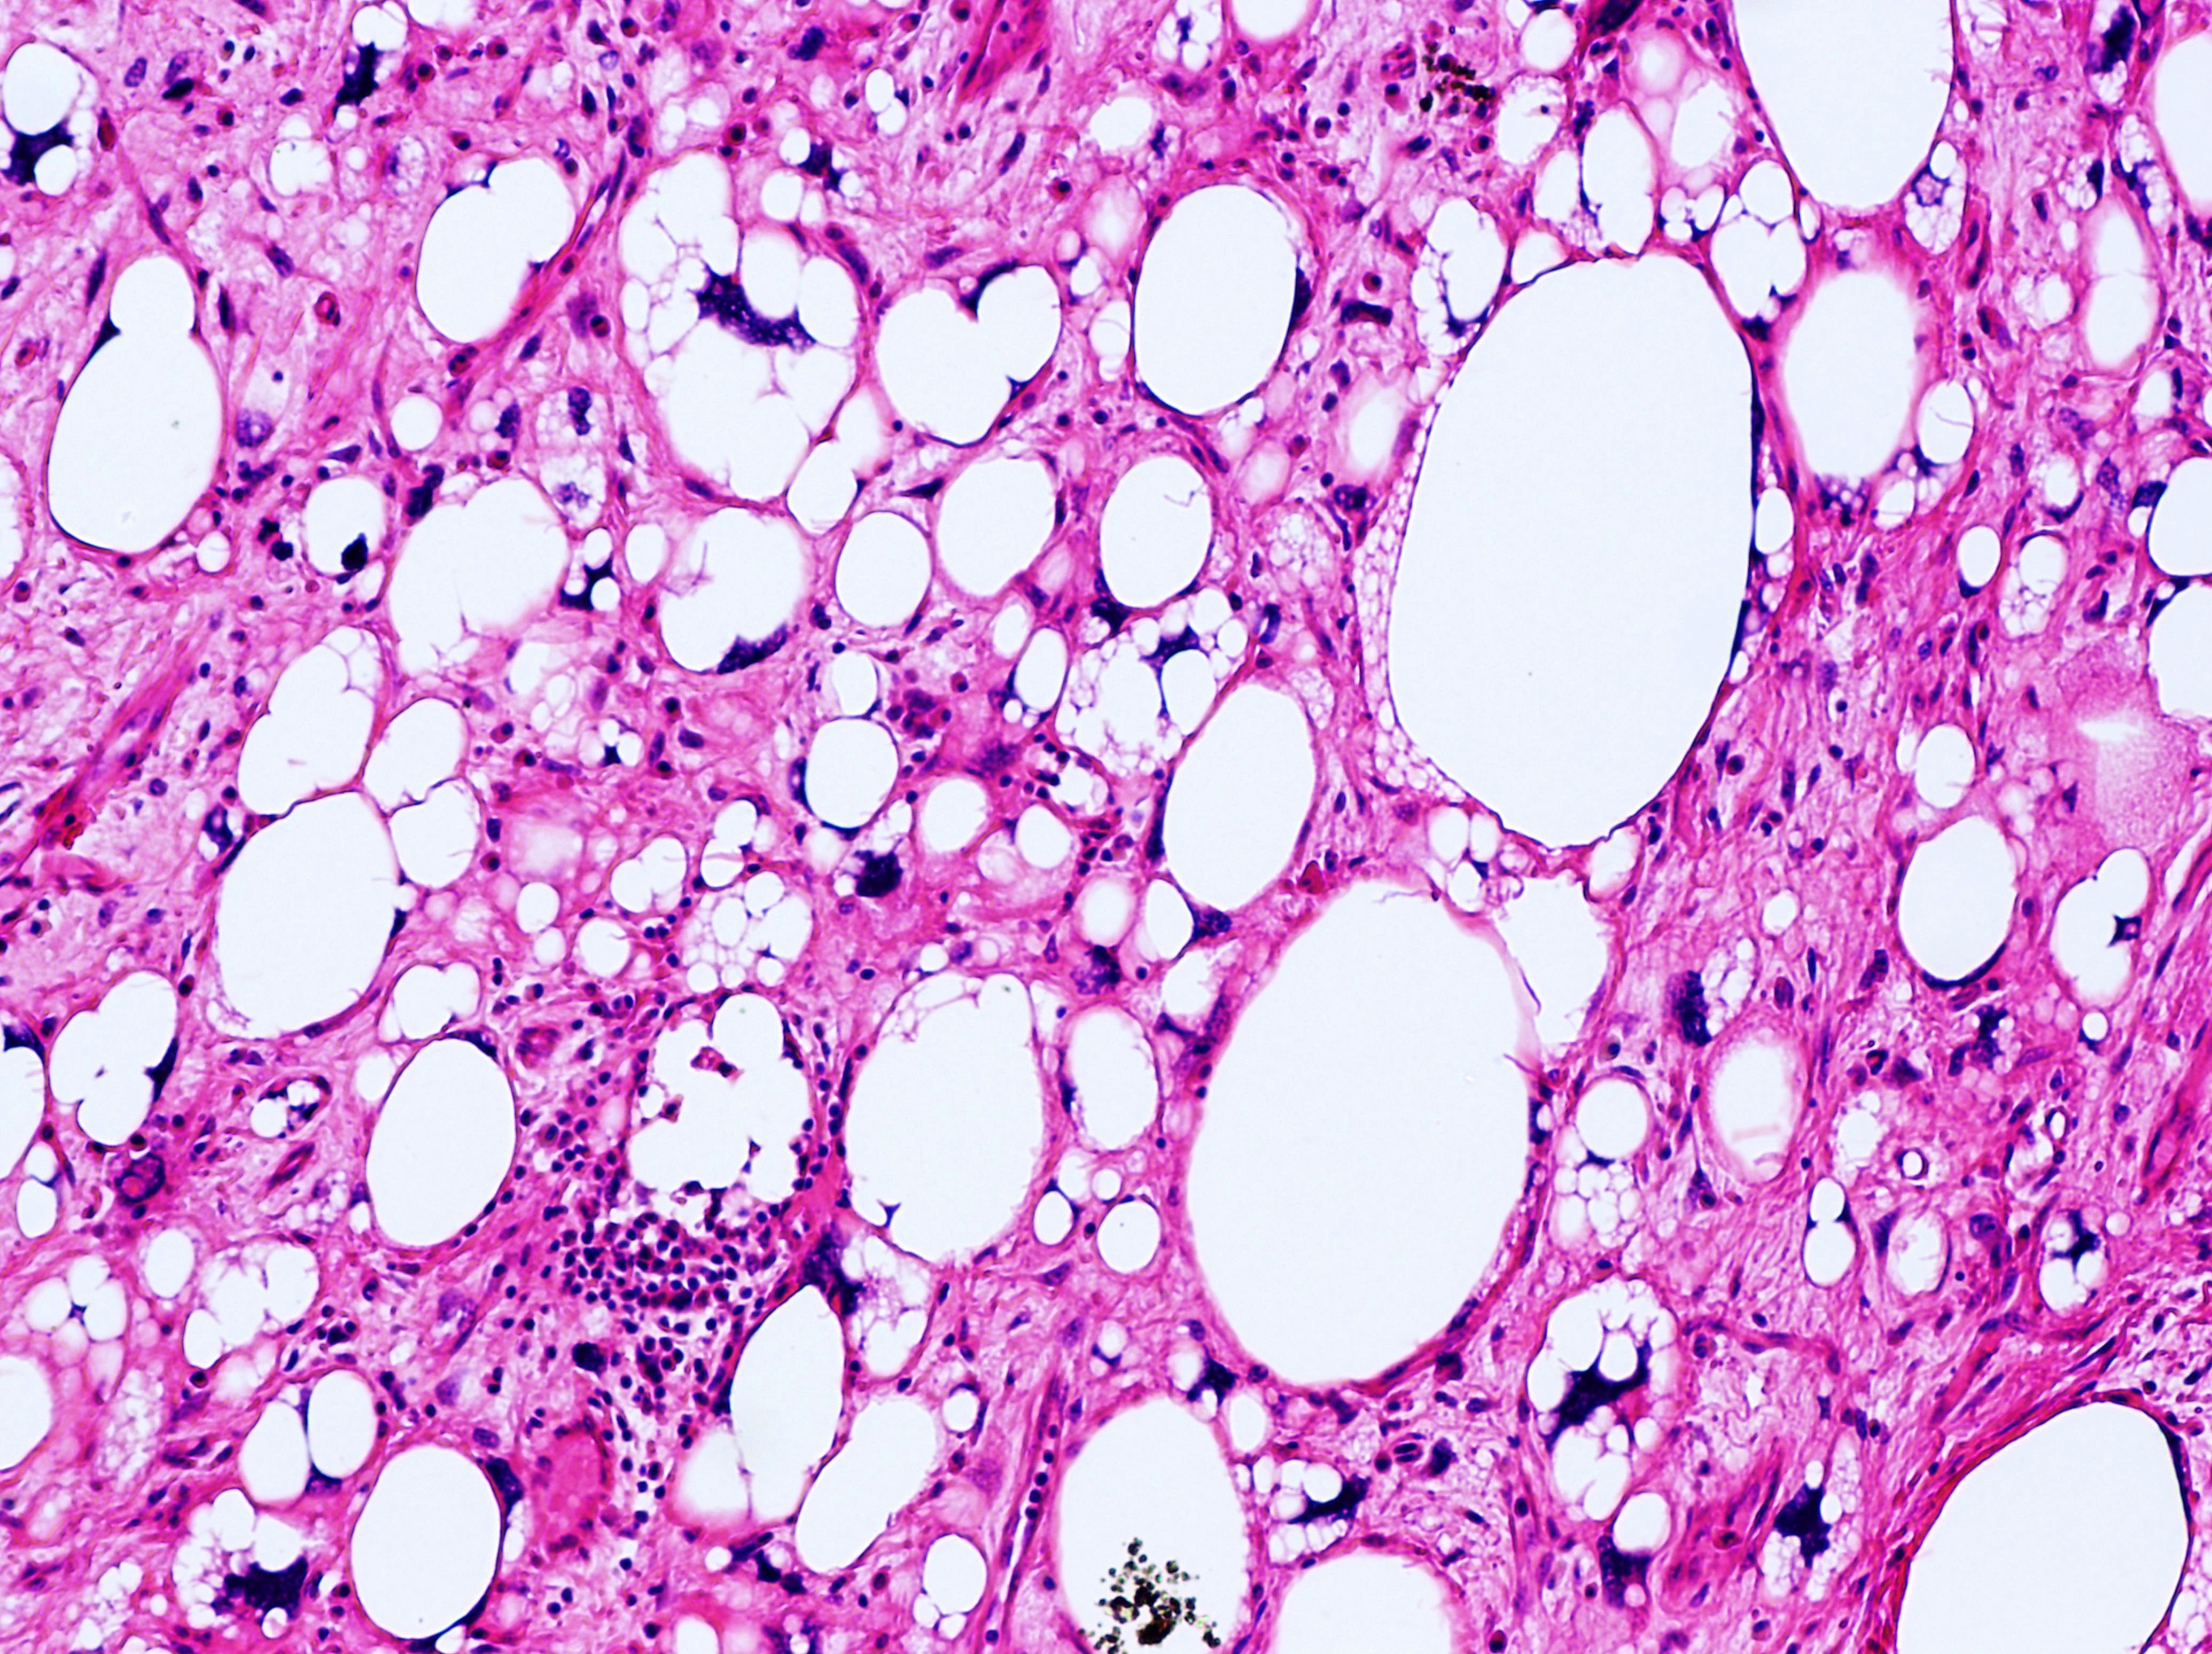

- Anatomical Pathology: This branch of pathology involves the examination of tissues removed from the body during surgery or biopsy to diagnose diseases such as cancer, infections, and inflammatory conditions. Anatomical pathologists analyze tissue samples under a microscope and may use various staining techniques to identify abnormalities.

- Cytopathology: Cytopathology is the study of individual cells obtained from body fluids or tissue samples. Cytopathologists examine cells under a microscope to detect abnormalities indicative of cancer, infection, inflammation, or other diseases. Common cytopathology tests include Pap smears for cervical cancer screening and fine needle aspiration (FNA) biopsies for diagnosing tumors.